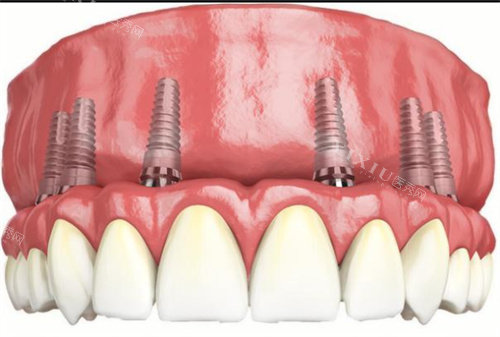

在技术层面,华普兰种植体的设计考虑了骨结合稳定性这一重要指标。良好的骨结合性能对于种植体的长期使用结果具有关键影响。该产品通过特殊设计来优化这一性能,但具体采用了哪些技术手段,目前公开资料中未见详细说明。

材料方面,华普兰种植体选用的是经过验证的生物相容性材料。这类材料在口腔环境中表现稳定,能够与人体组织良好共存。不过,关于材料的具体成分、机械性能等详细参数,建议向可靠机构或生产商进一步询问确认。